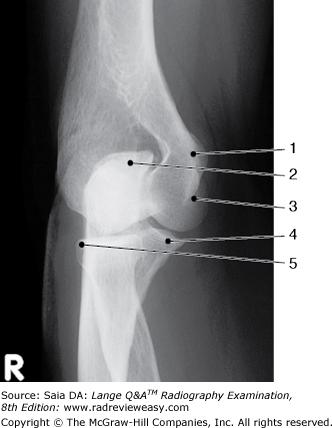

Identify the structure labeled 1 in the AP projection of the knee shown in Figure 2–16.

A Lateral condyle B Lateral epicondyle C Medial condyle D Medial epicondyle

Medial epicondyle

The structure labeled number 4 in Figure 2–41 is the

coracoid process

What is the name of the structure indicated as number 5 in Figure 7–7?

Olecranon fossa